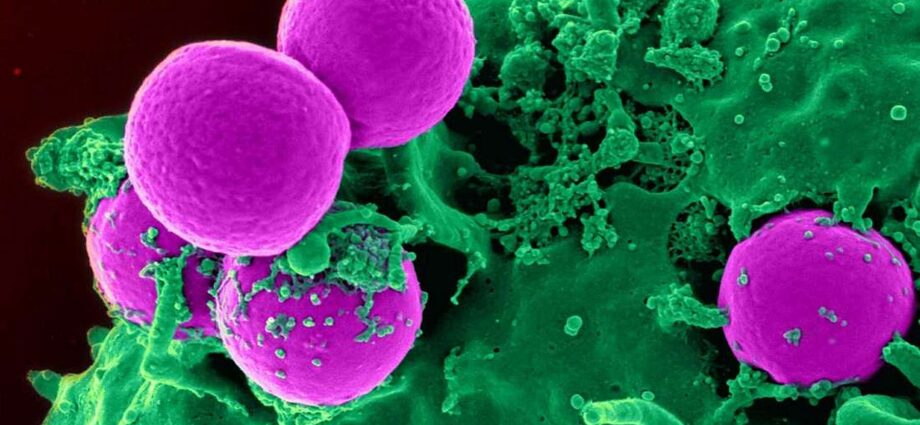

Le corps des êtres vivants tels que des animaux et des hommes possède une incroyable quantité de cellules, environ 100 000 milliards au total. Par conséquent, il est en état de renouvellement cellulaire permanent, à partir de la naissance jusqu’à la mort. Il est en quelque sorte constamment remis à neuf.

Pratiquement tous les organes, tous les tissus et toutes les cellules sont soumis à ce renouvellement cellulaire permanent et vont être complètement régénérés plusieurs fois dans une vie, à une fréquence plus ou moins élevée en fonction des cellules. Ce qui fait qu’au bout du compte, l’immense majorité des cellules et des organes sont plus jeunes que l’individu lui-même.

Ce vaste écosystème cellulaire – qui est finalement notre organisme – contient environ 250 types de cellules différentes. La grande majorité est soumise au renouvellement cellulaire, sauf quelques exceptions, comme, par exemple, les neurones et les cellules cardiaques où le renouvellement est très lent ou quasi inexistant.